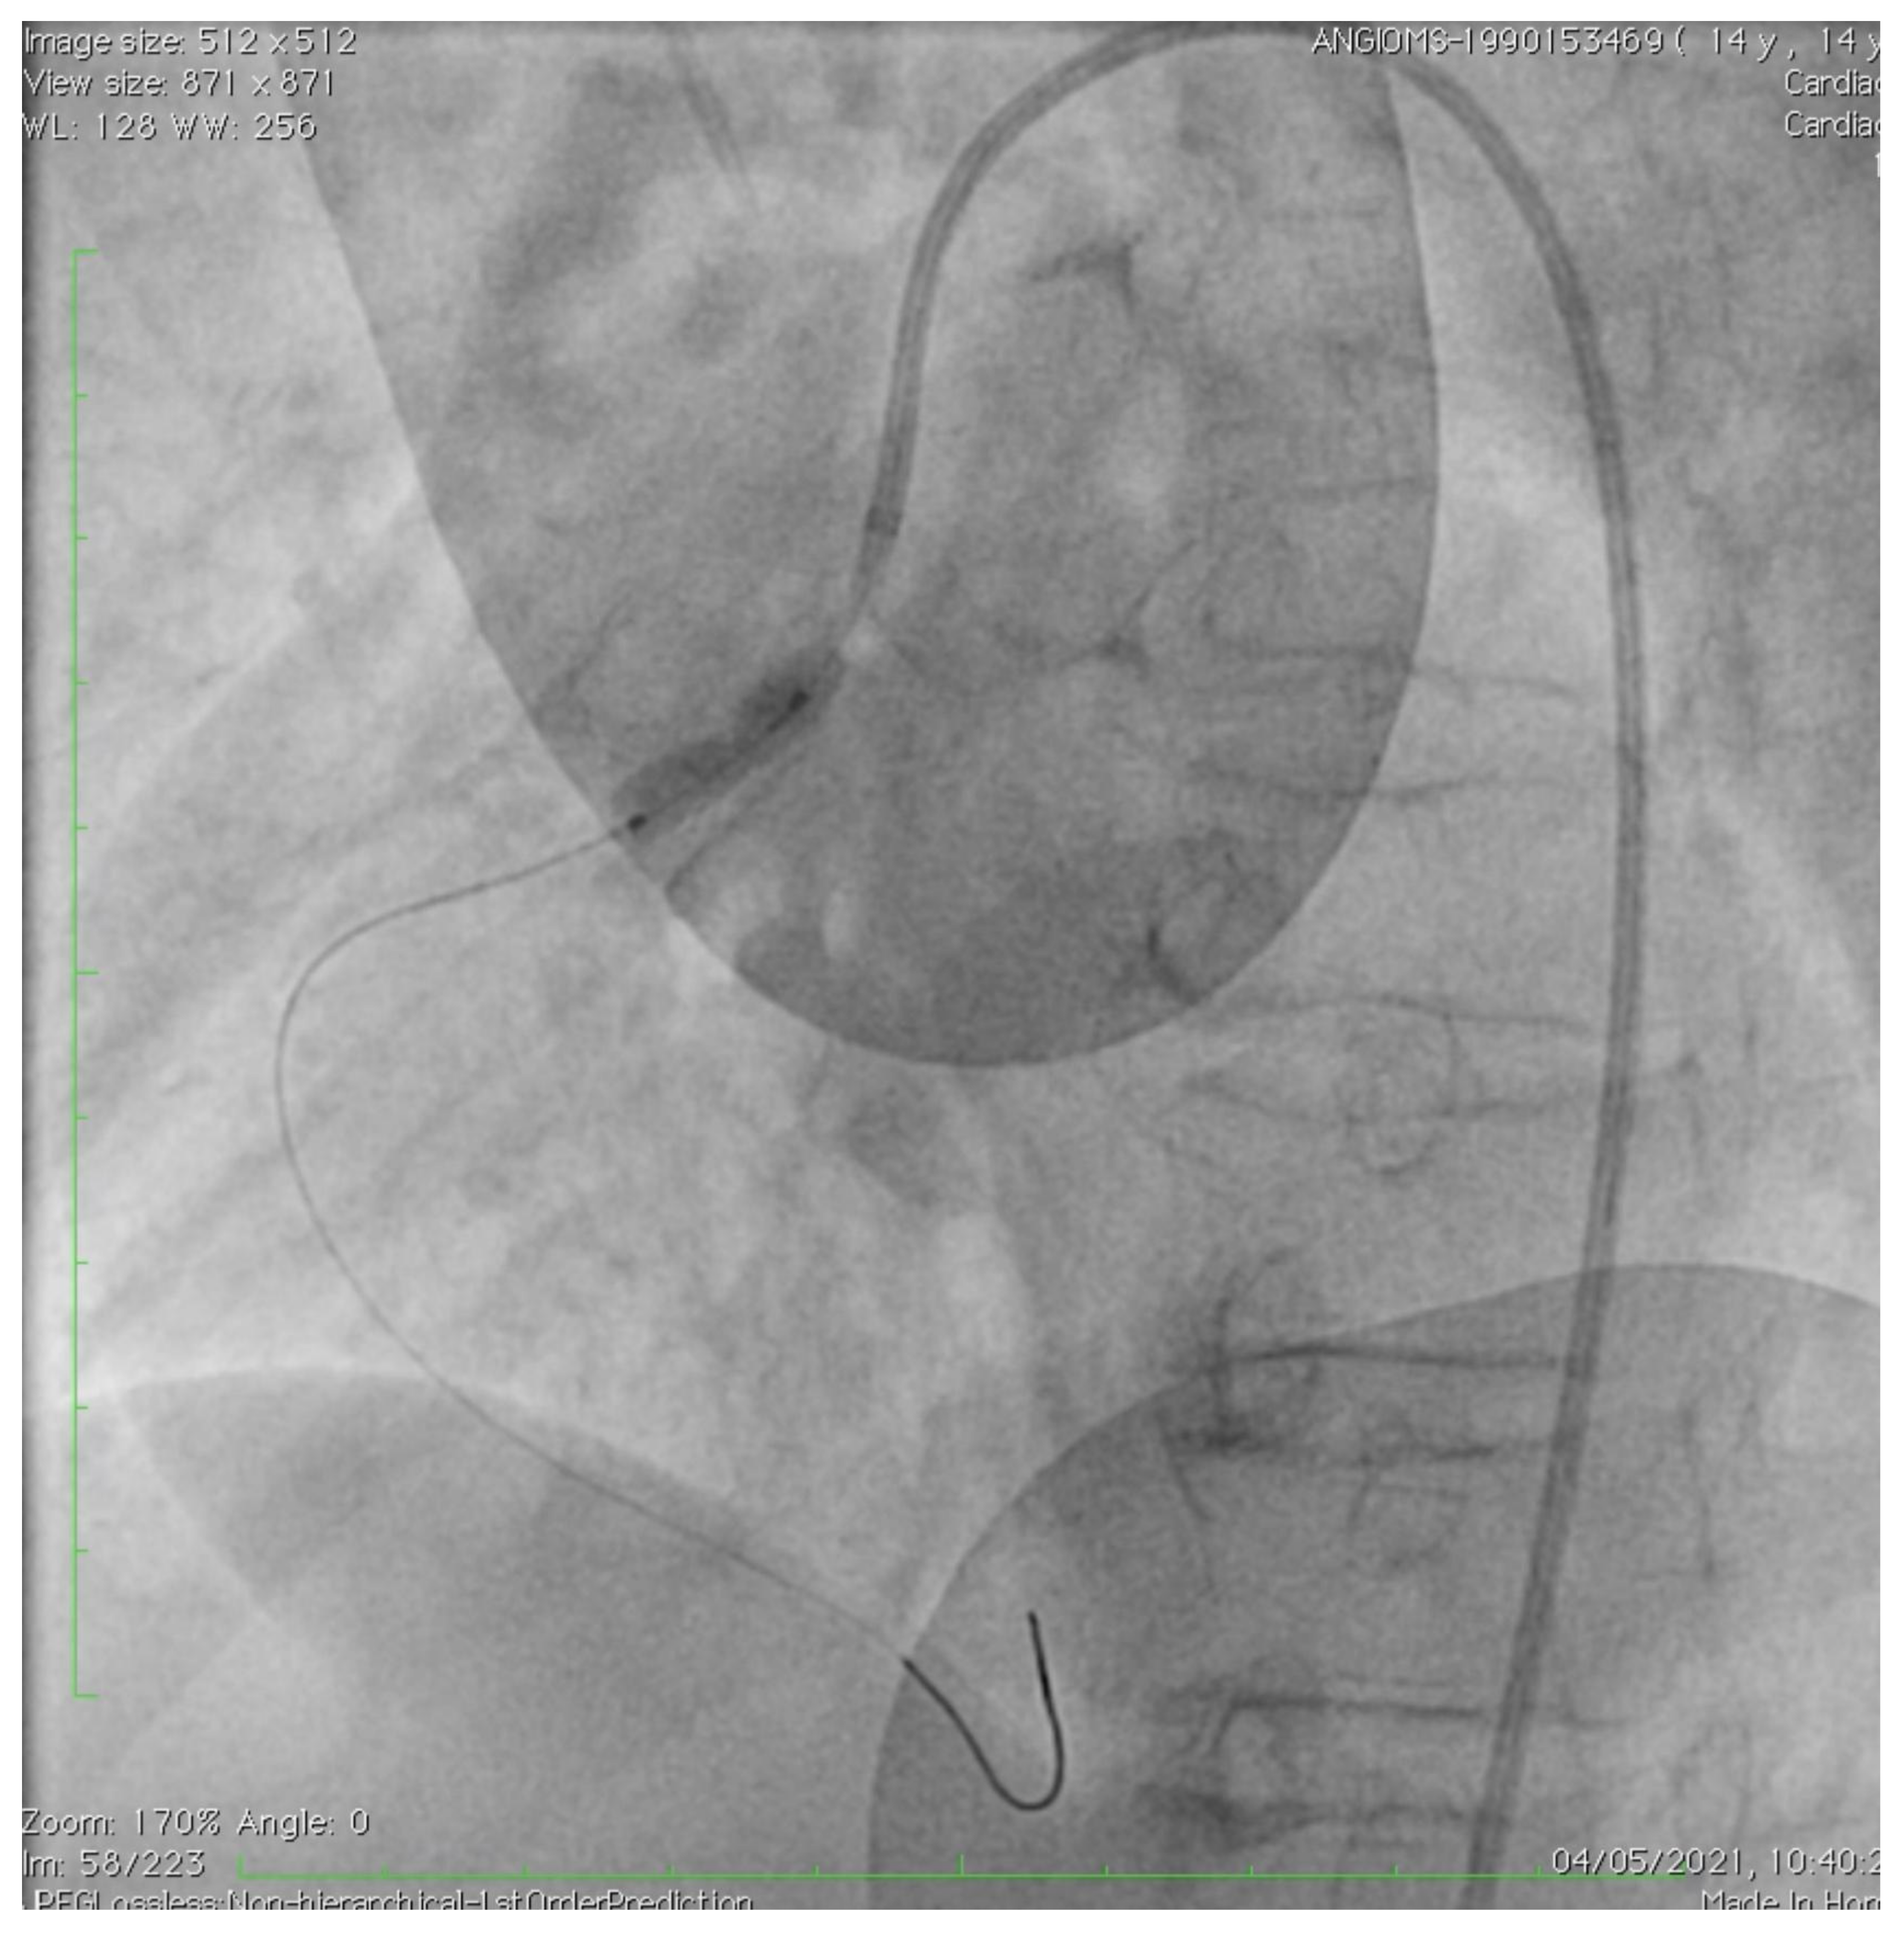

2. Case Description

- Roggen, M.; Dubois, C.; Gewillig, M. Coronary artery stenting in a patient with progeria. Catheter. Cardiovasc. Interv. 2017, 90, E38–E40. [Google Scholar] [CrossRef] [PubMed]

- Callahan, R.; Lock, J.E.; Shah, P.B.; Marshall, A.C. Transcatheter intervention of coronary ob structions in infants, children and young adults. Pediatr. Cardiol. 2018, 39, 1299–1307. [Google Scholar] [CrossRef]